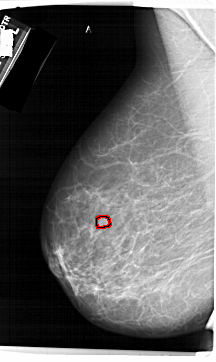

A_1423_1.RIGHT_MLO

RIGHT_CC LINES 5896 PIXELS_PER_LINE 3451 BITS_PER_PIXEL 12 RESOLUTION 43.5 NON_OVERLAY

FILE: A_1423_1.LEFT_CC.OVERLAY

TOTAL_ABNORMALITIES 1

ABNORMALITY 1

LESION_TYPE MASS SHAPE LOBULATED MARGINS CIRCUMSCRIBED

ASSESSMENT 4

SUBTLETY 3

PATHOLOGY BENIGN

TOTAL_OUTLINES 1

BOUNDARY